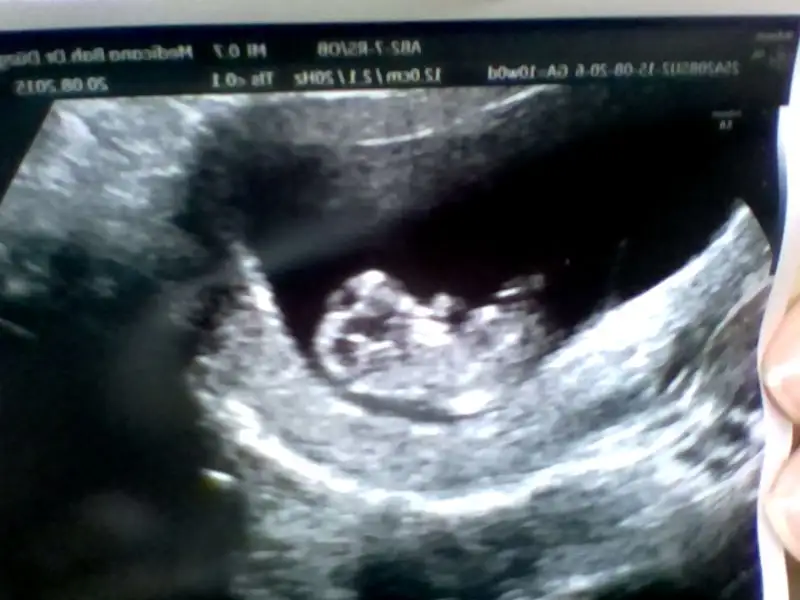

Bilmiyorum ki belkide saka yapmıstır o anda heyecandan anlayamadım :) esimle bayagı gülüsmeler falan oldu 10+1 mis bugün lokumcum

Masallahhh lokumuna :)) benimki 9+3 bugün. 5gun varmis o zaman :) neyse bi dahaki gorusmemizde bizim için dans edeceklerine eminim ben :)))